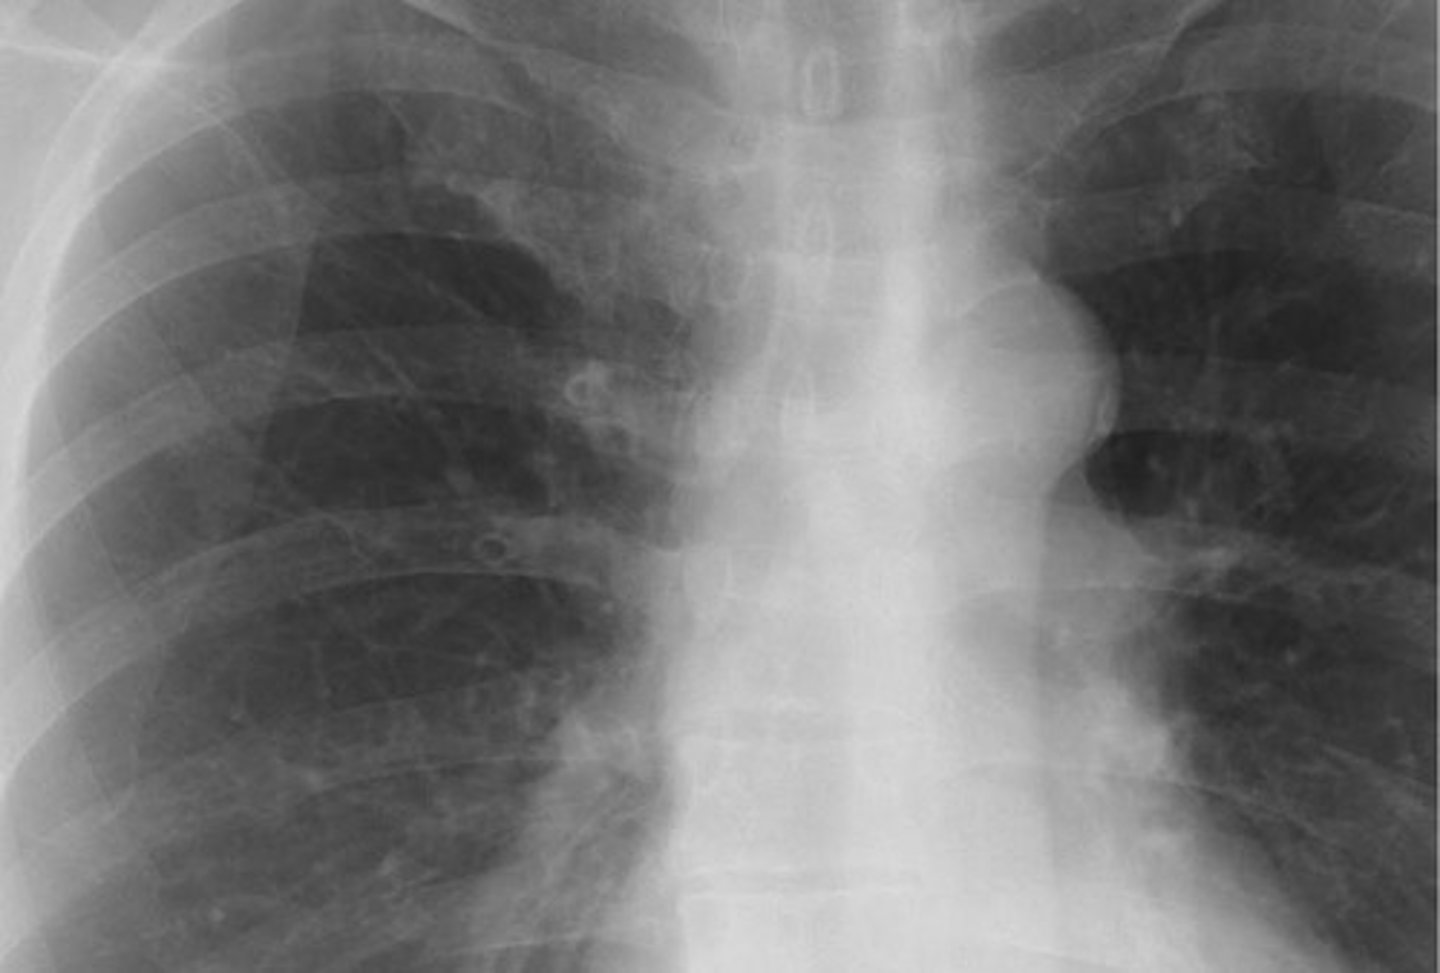

-obscured the left heart border and diaphragm

Lingular pneumonia appearance

(PICTURE ON LEFT)

Pulmonary edema appearance